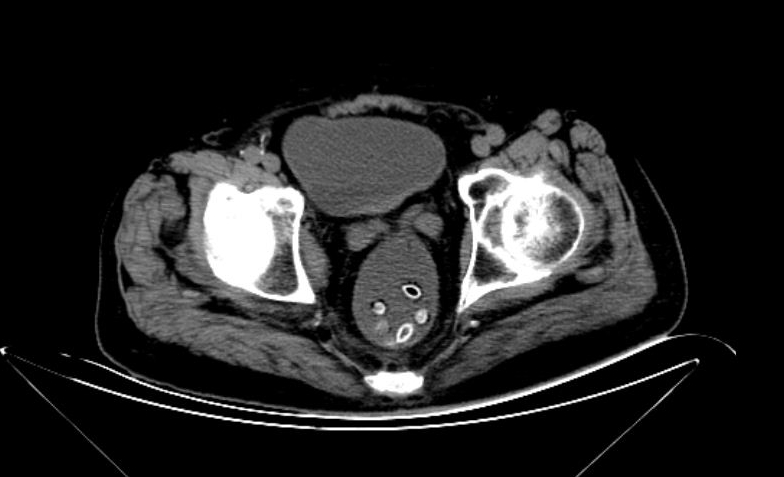

87岁的洪大爷,因脑梗死、高血压于7月2日入住玉环市人民医院。不料,第二天就出现了胃口差、腹部胀痛、排便困难等问题。予以CT检查发现,洪大爷下腹部一串“珠子”。

“以前生活苦,父辈们吃水果都不吐籽的,至今还有不少人保留着这个习惯。”神经内科主治医师刘青霞介绍,那堆“珠子”洪大爷未吐的杨梅籽,在肠道里堆积导致肠梗阻。

外科主治医生郑胜利会诊,从他肛门抠出8颗杨梅籽,才解除了肠梗阻的危机。经灌肠处理后,老人才得以舒坦。